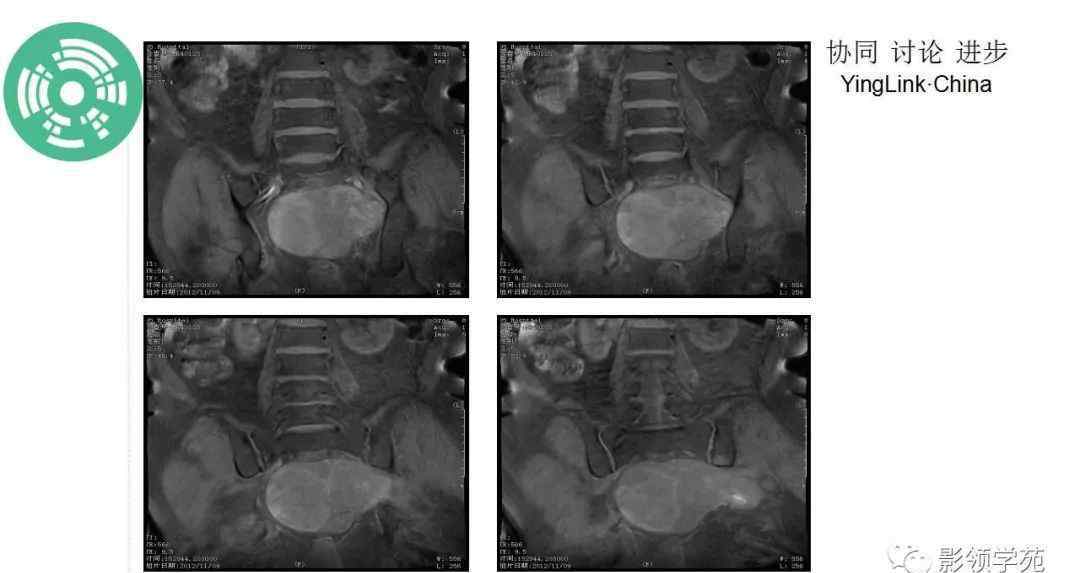

MR: T1W1序列呈低信号或等信号,小病灶高信号代表肿瘤出血或粘液蛋白。T2W1序列显示中等或明显的高信号强度,内部低信号强度代表钙化、纤维隔膜或血液降解产物。增强后呈中、重度增强,偶有轻度或无增强,动态增强呈缓慢、持续增强。